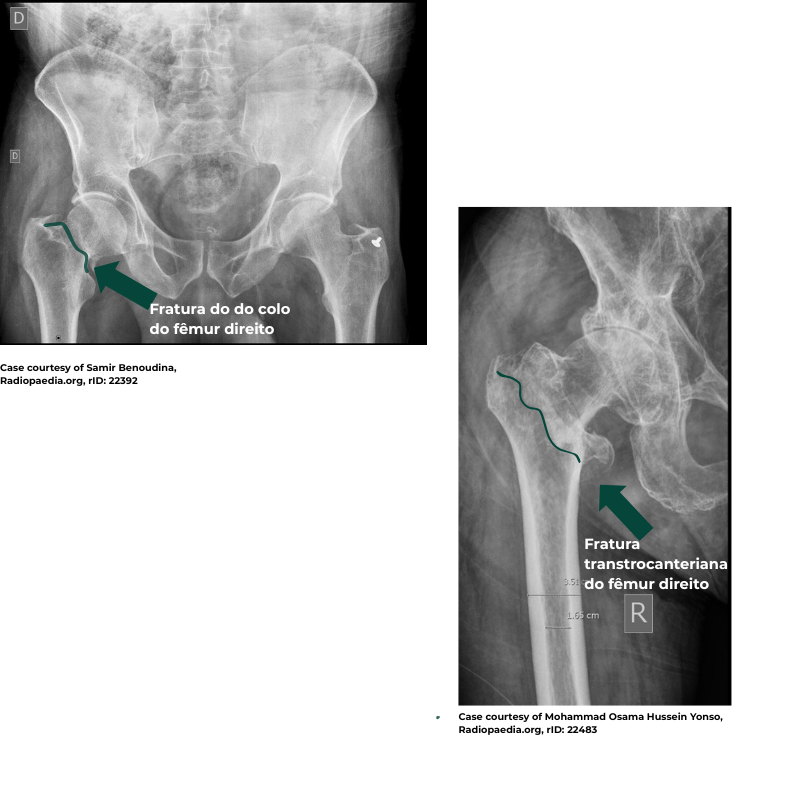

A localização da fratura colo do fêmur, região transtrocanterica ou subtrocanterica- isso é determinante para definir o tipo de tratamento e a técnica cirúrgica mais adequada.

As fraturas são nominadas conforme a localização do osso que acometem, podendo ser:

- Colo do fêmur

- Região transtrocanterica

- Região subtrocanterica